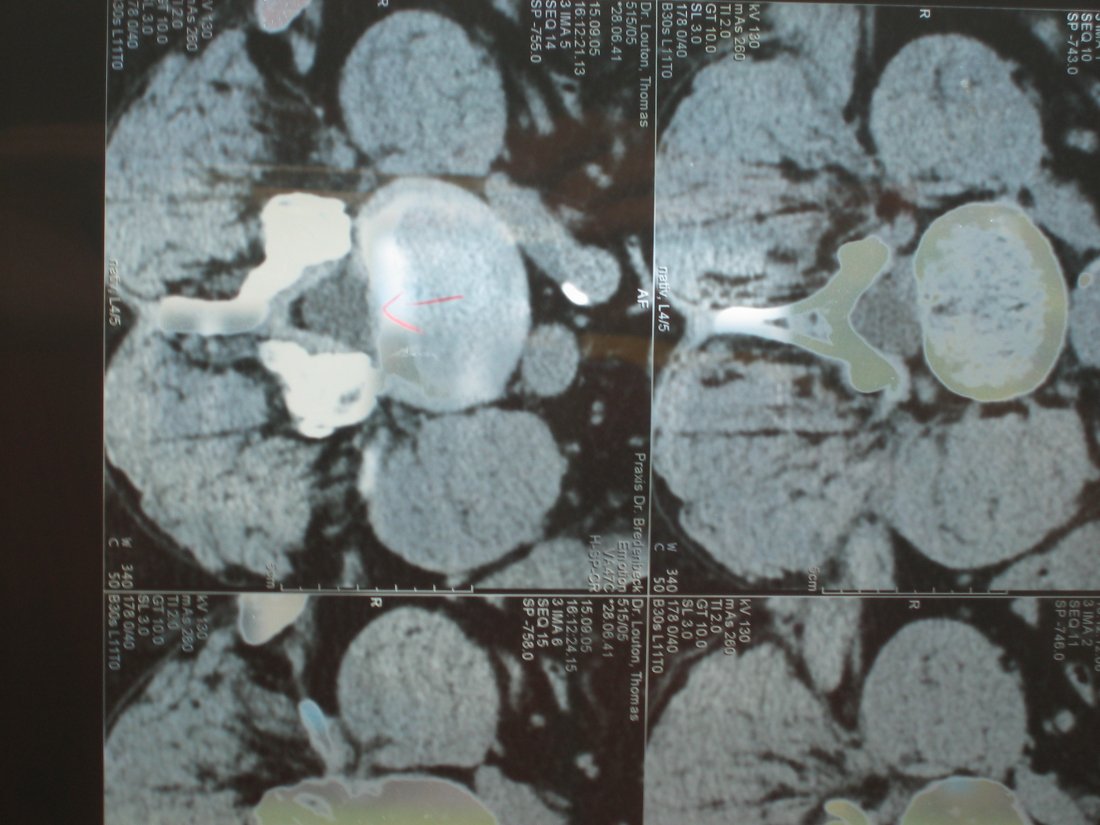

After the fall I discovered that I had a slipped disk. Here you can see the problem. Gladly, this did not require anything but rest and care.